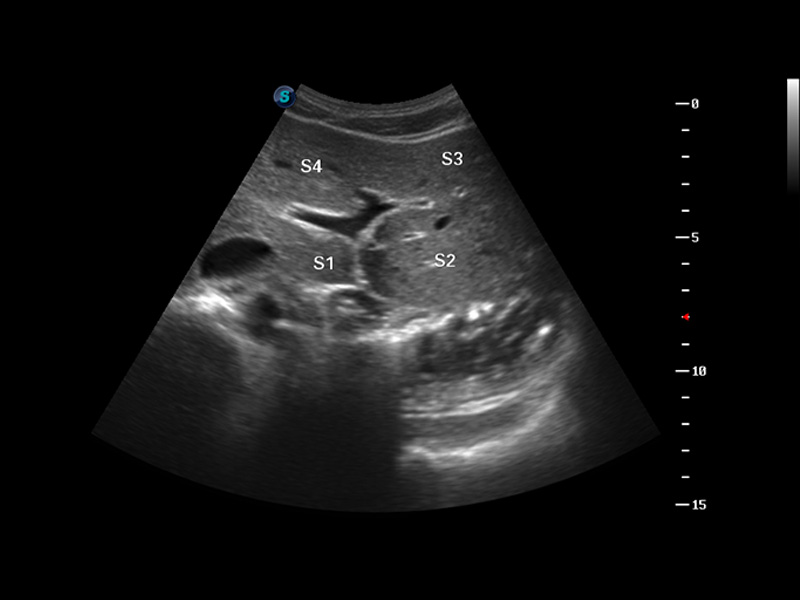

S8 EXP便携式彩色多普勒超声诊断仪是哈哈体育官网研发的高端全身应用型便携彩超。高通道的VIS平台融合可视化(Visual)、智能化(Intelligent)和人性化(Smart)的特点,配以哈哈体育官网自主研发生产的探头大家族,使您能够快速、准确的获得病人信息,提高工作效率的同时减轻疲劳。

谐波成像